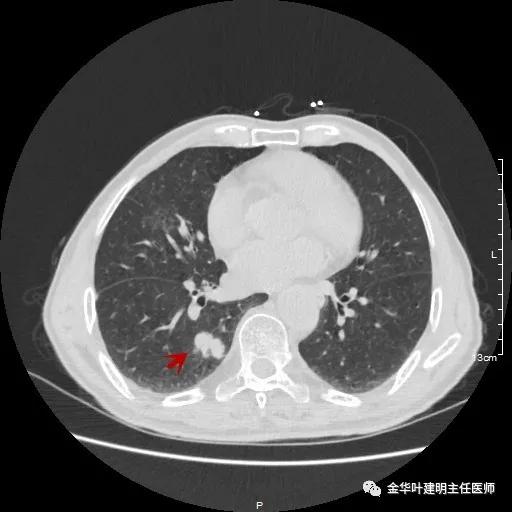

金华的某A,今年已经80岁了,前些天检查发现右下肺部占位,让我会诊。我打开电脑一看图,发现右下肺是典型的实性分叶状的占位,基本可肯定肺癌,余肺仍有多处磨玻璃影及类似慢性炎的病灶,是不是合并炎症?还是多原发肺癌?鉴于其中叶肺门部混合磨玻璃结节边缘略显模糊,为了防止炎性病灶,让其进行了10天的静脉抗炎治疗,但复查靶扫描后发现病灶无任何吸收好转,靶扫描上把细节显示的更清楚了,反而更坚定了我判断其为肺癌的结论。对于这样年纪的多原发癌,我们该如何来进行临床思考呢?治疗该如何建议与决策?当然最后的结果要如实告知患方后,由他们自己决定。

以上示右中叶病灶4。也是囊腔型病灶,病灶大,囊壁是磨玻璃密度,亦是较为典型的囊腔型肺癌影像。单病灶看,需中叶切除来治疗,因病灶3的存在,中叶切除可同时解决病灶3与病灶4。